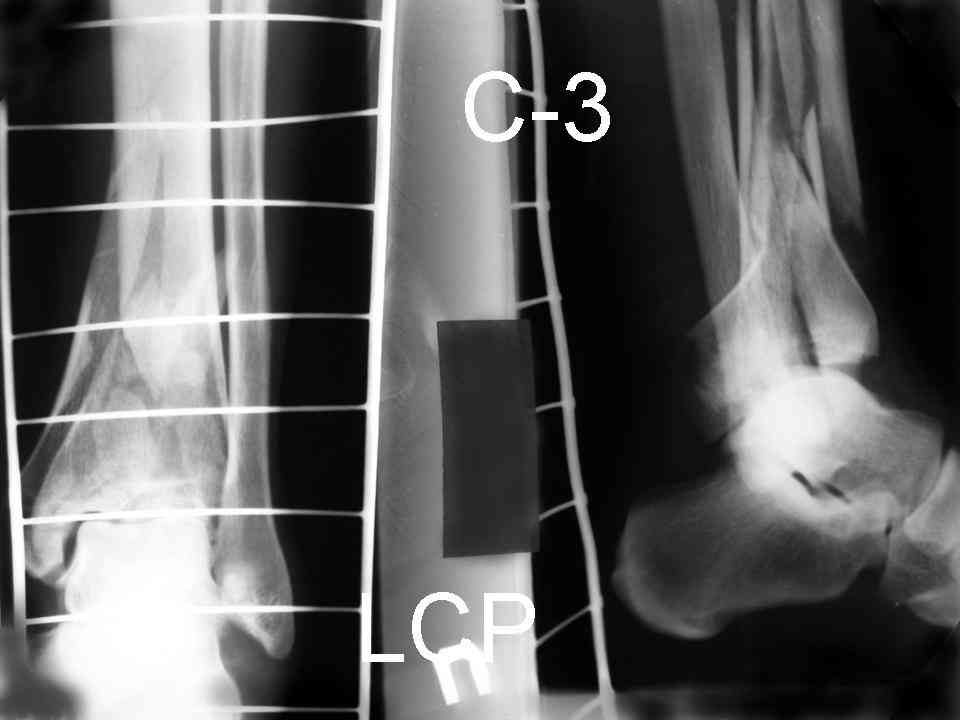

Это типичный перелом пилона, который надп лечить только открыто.Извини те что опоздал к обсуждению, но даже если вы уже оперировали больного по Илизарову это даже лучше.Посылаю картинки.

Посмотрим вроде прошло если понравится напишите расскажу как это сделать.По принципам АО кстати при поступлении сначала восстанавливают длину малоберцовой кости фиксируют пластиной 1/3 трубки потом накладывают аппарат наружной фиксации и через 7-10 дней открыто восстанавливают большеберцовую кость.С уважением Дрягин

На рентгенограммах типичный перелом пилона по типу С-3. есть опыт до 100 открытых опреаций у нас в клинике. 20 примерно в год. Принцип один -все внутрисуставные переломы нуждаются в открытой репозиции и внутренней стабильной фиксации. При поступлении КТ не надо, так как получается только нагромождение костей. Истинной картины нет. Главное восстановить длину малоберцовой кости - это ключ к успеху. При поступлении меньше всего надо думать о сосудистых расстройствах, т.к. сама операция и репозиция даже сначала частичная даёт улучшение сосудитых нарушений. Причём очень быстро. Операция в 2этапа. При поступлении доступ позади наружной лодыжки, причём обязательно. После этого репозиция малоберцовой кости и фиксация пластиной 1/3 трубки под винт 3,5. Дренаж и любой аппарат наружной фиксации. Затем после спадения отёка на 5-7-10 день аппрат снимается и дугообразный разрез спереди от медиальной лодыжки 10-12 см. Главной чтобы расстояние между 1 и вторым разрезом было не меньше 7-8 см. Тогда не будет некрозов лоскутов. Таранная кость используется как матрица на неё укладываются отломки и фиксируются пицами. Ренг-контроль. Отломки лежат все отдельно, но ничего не высыпется. При переломах С-3 всегда нужна костная пластика (из крыла). Фиксация пластиной лист клевера простой или LCP. Гипс не нужен. Дренаж до 48 часов. Операция длится 3-4 часа обязательно без жгута. Посылаю примерно такой же случай.